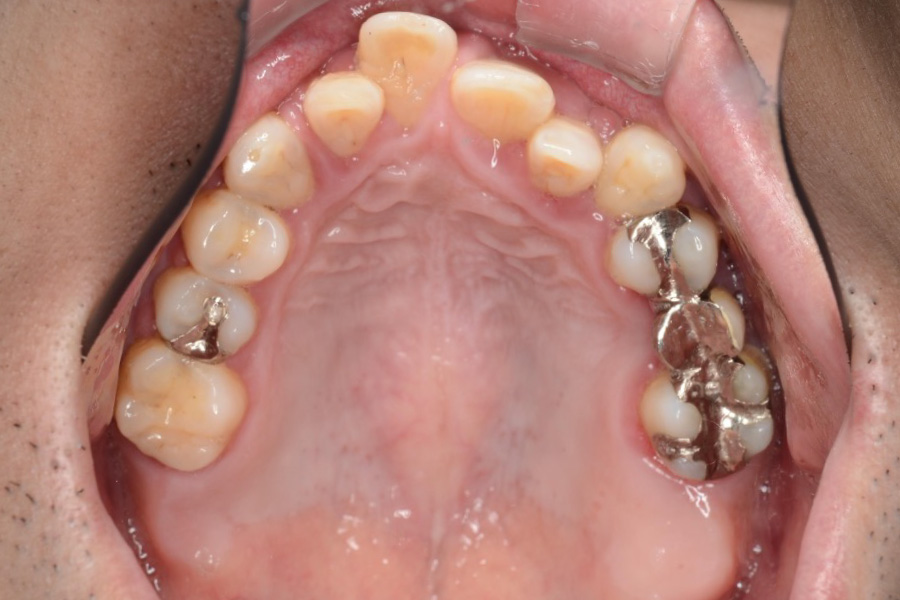

治療後

主訴 上の前歯を揃えたい

治療内容 インビザライン矯正

小臼歯抜歯

治療に伴うリスク 矯正終了後は、リテーナーを指示通りに使用し、歯の後戻りを防ぐ必要があります。